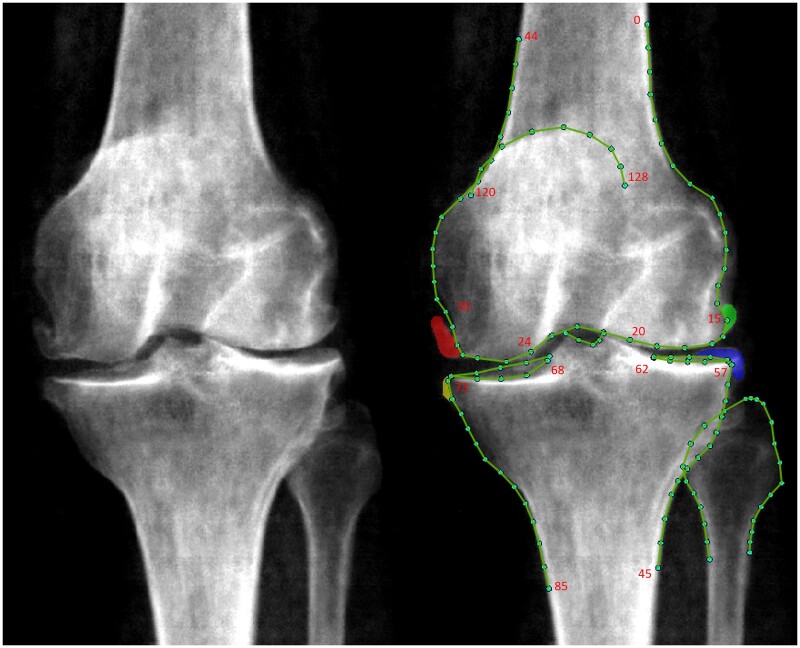

Methods: Right knee DXA scans were manually annotated for osteophytes to derive corresponding grades. Joint space narrowing (JSN) grades in the medial joint compartment were determined from automatically measured minimum joint space width. Overall rKOA grade (0-4) was determined by combining osteophyte and JSN grades. Logistic regression was employed to investigate the associations of osteophyte, JSN and rKOA grades with knee pain and hospital-diagnosed KOA. Cox proportional hazards modelling was used to examine the associations of these variables with risk of subsequent total knee replacement (TKR).